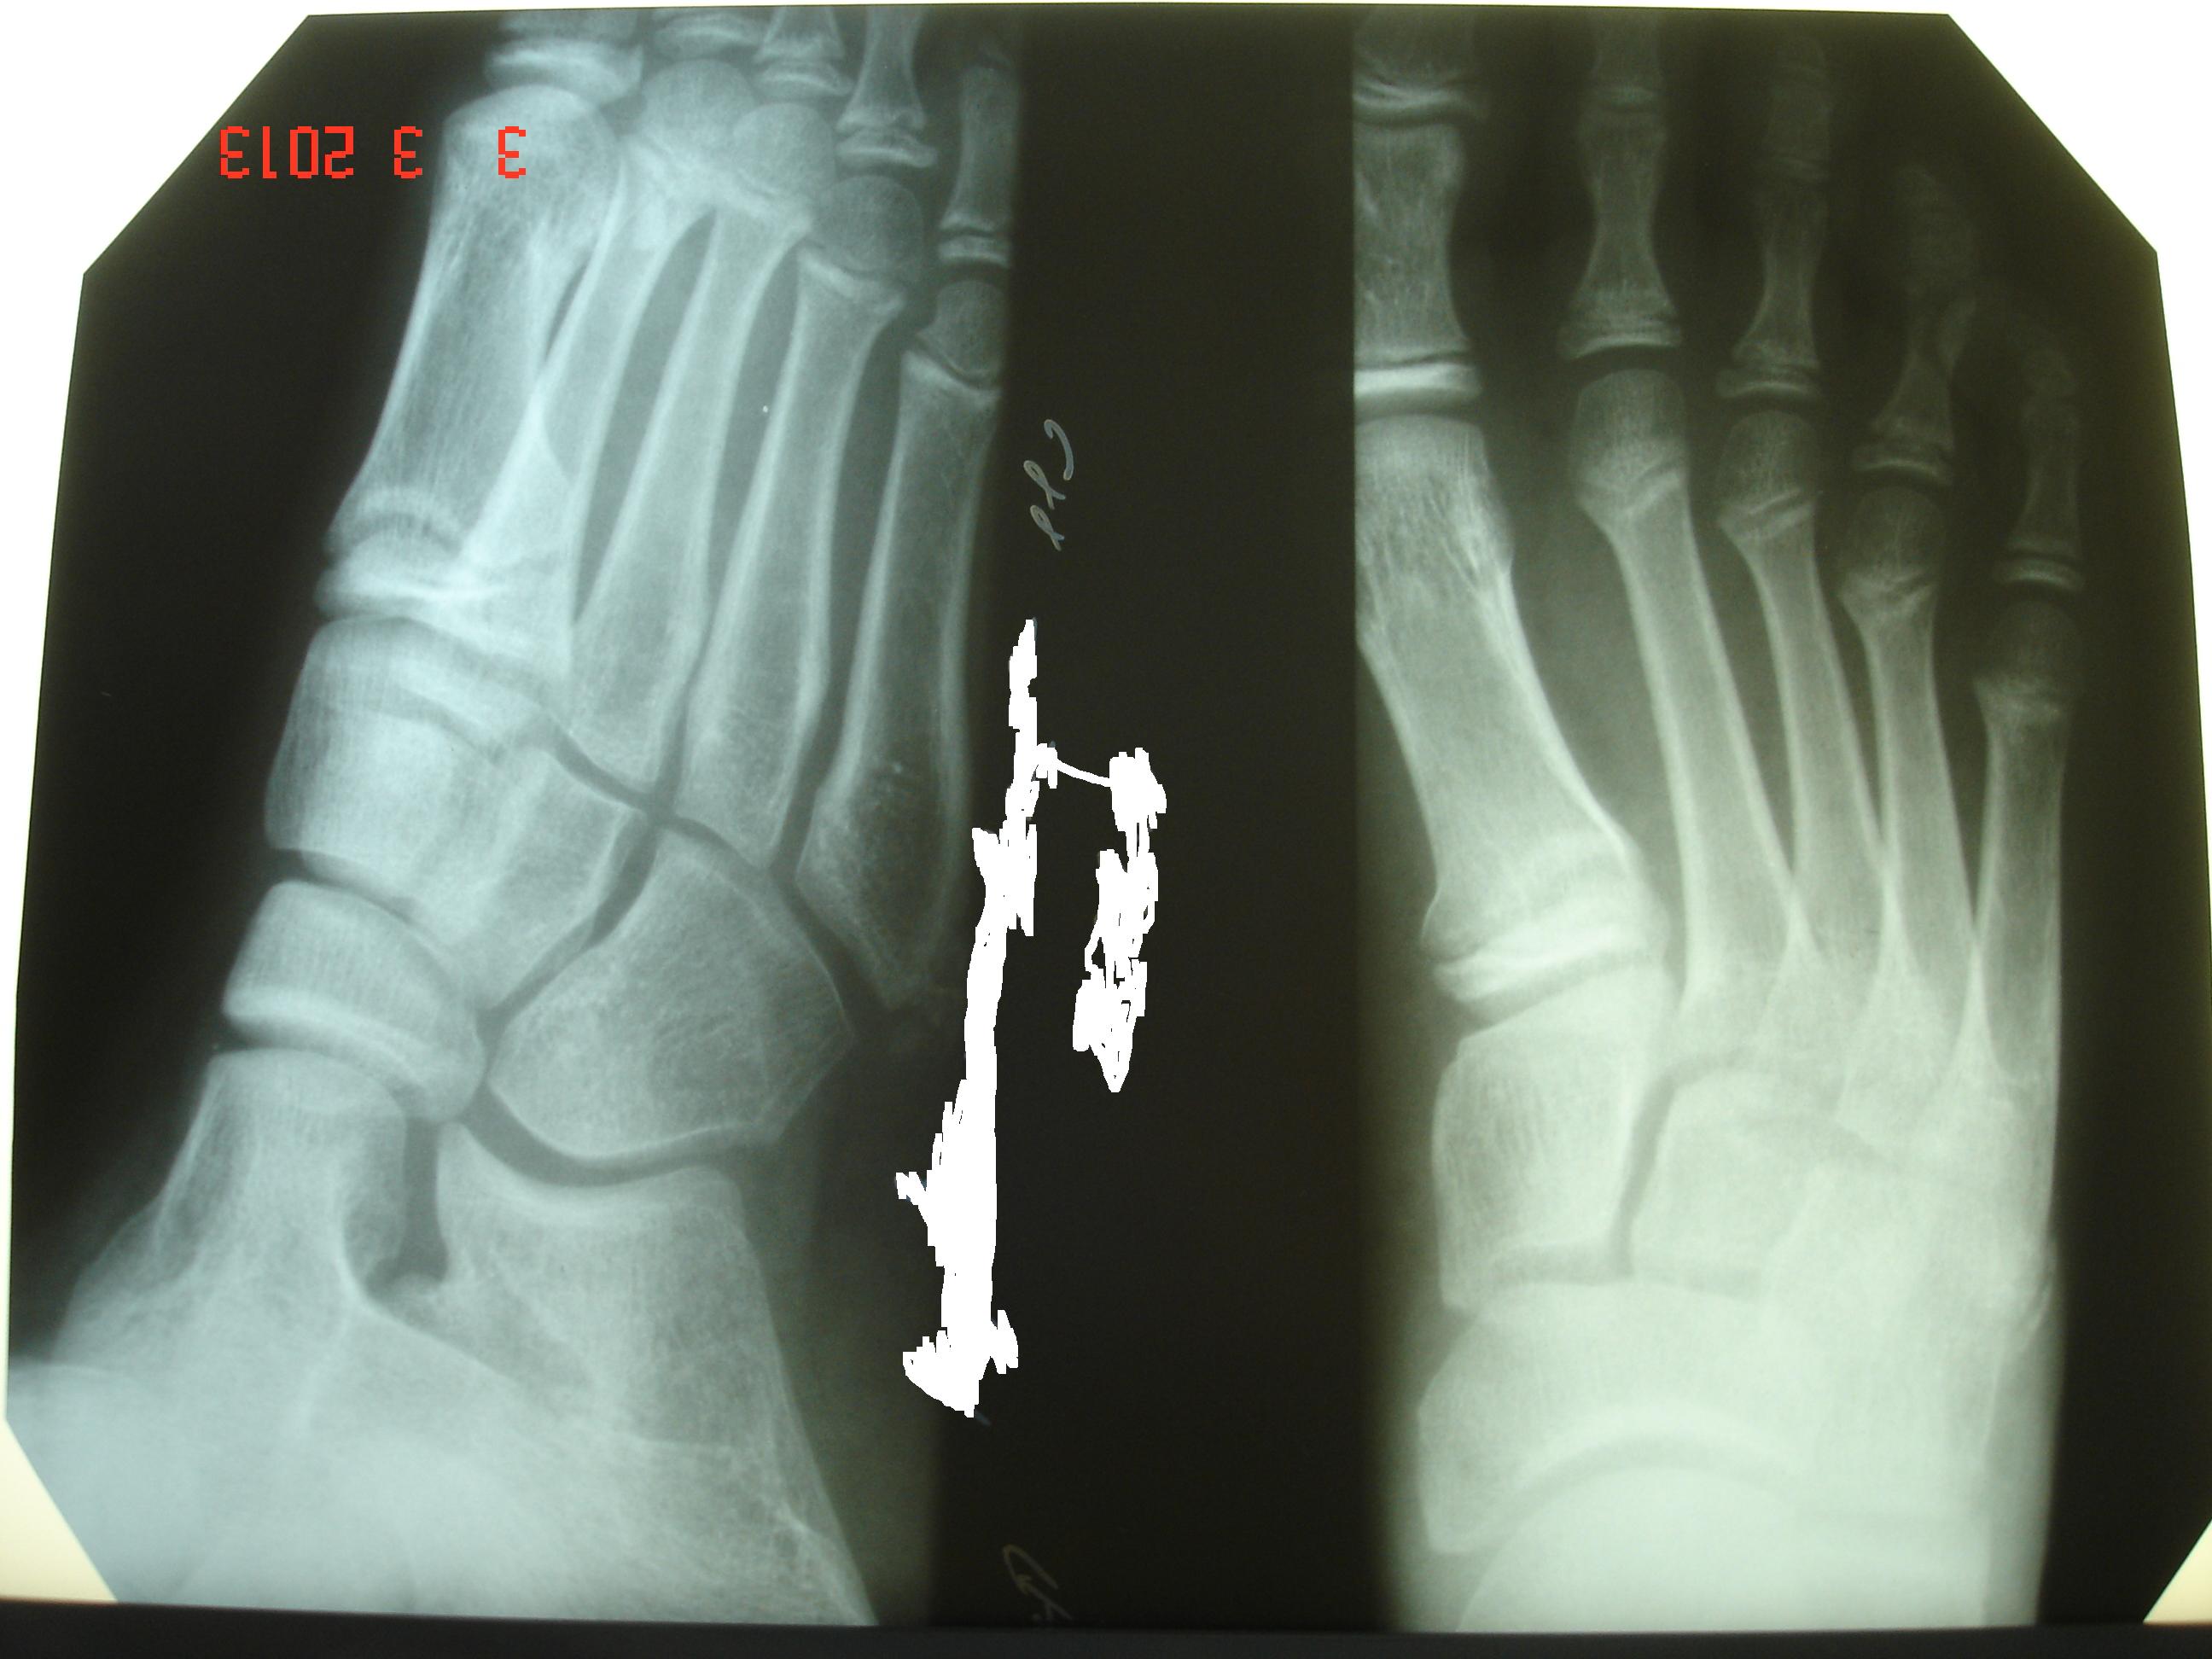

Мальчик, 11 лет. Обращение в травмпункт с жалобами на боли в правой стопе. Упал на горке. «Мозговым штурмом» этот случай назвать будет слишком громко. Так, легкая разминка перед тренировкой. Прошу извинить за качество снимков, но патологию (в общем и целом) видно.

Перелом основания I плюсневой. Нечасто встретишь...

перелом основания 1 плюсневой кости по типу остеоэпифизеолиза, в травмпункте у детей встречается не редко, раз в неделю точно есть))) остальное здесь - возрастная норма

В данном случае имеется деформация кортекса и нарушение балочной структуры прилежащей к зоне роста внутреннего сектора метадиафизарной зоны, по типу "сминания" кости. Высока вероятность того, что перелом вхож в ростковую зону, медиальный сектор ее шире, нежели остальная часть физарной линии. Скорее всего, повреждение её здесь есть, частичное. Наблюдать в динамике рост кости обязательно, хотя, думаю, принципиального влияния на форму и длину кости данная травма не окажет.

Что же касается обсуждаемого случая - на мой взгляд, зону роста он совсем не затрагивает, имеет место сминание кости по типу "зелёной ветки".

Измерения в прямой проекции показывают некоторое превалирование ширины зоны роста А (медиальный сектор) над проекционно расходящимися тыльным и подошвенным секторами (В, С).

Но что же делать со второй картинкой?! Прошу объяснений.

А что там на второй картинке, то что вы показываете, на мой взгляд, к перелому никакого отношения не имеет. Перелом вот здесь

. Наложение теней, локальное разрежение костной структуры, наложение костных балок... Сложно сказать. На мой взгляд, линией перелома эта линия является вряд ли. Во-первых, она (синие стрелки) продолжается и на медиальную клиновидную кость (красный пунктир), перелом которой в данном случае совместно с I плюсневой предположить вообще очень сложно. Во-вторых, подобные линии можно найти и на других участках снимка (зелёная стрелка).